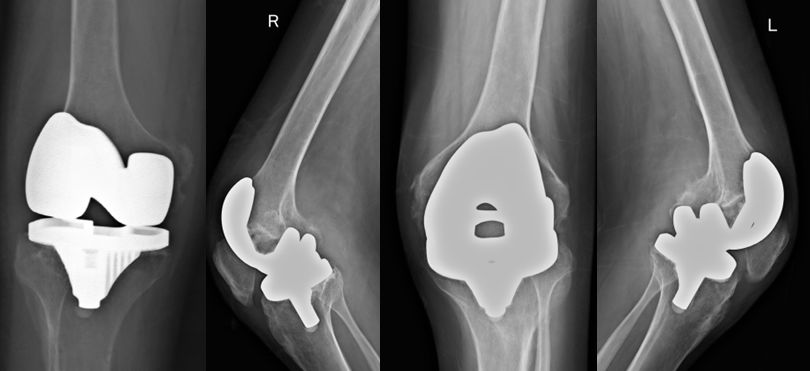

例1:行双髋关节置换后疼痛明显缓解,关节活动明显改善

例2:行双髋、双膝关节置换后疼痛明显缓解、恢复行走功能